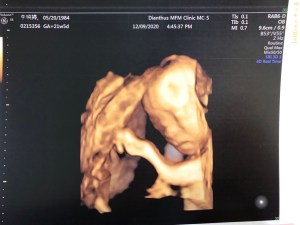

被超音波技術員阿姨擠壓了1個小時,但,這臉部表情也太…

臉皺成這樣,大家都說像個老頭了~

做超音波的前一天,跟藍天溝通了明天會花很多時間照超音波,但是我沒想到對寶寶來說,是一直被擠壓,是被打擾的。一開始很配合,還有在活動,最後技術阿姨要數藍天的右手指時,他的手剛好握拳放在臉上,讓阿姨不容易數手指,機器只好壓來壓去、轉來轉去的看,他真的不喜歡,臉臉一直被擠壓的感覺阿。一臉告訴我們他的不喜歡~